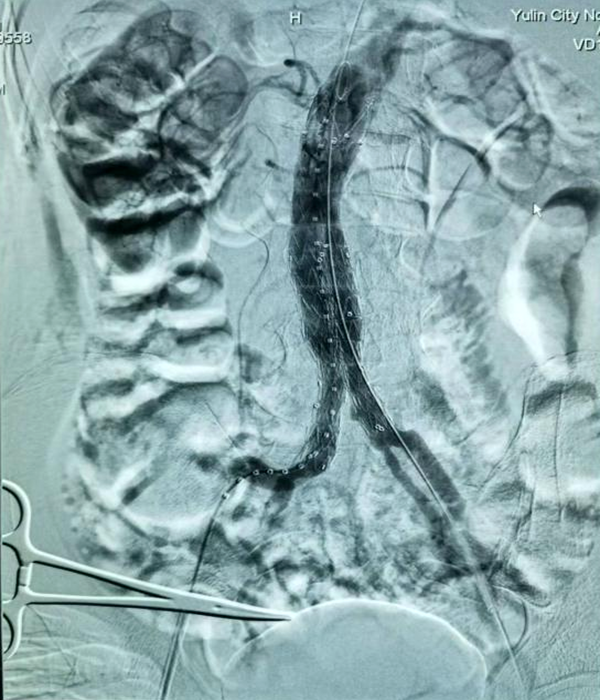

到达榆林二院后,急诊科立即启动绿色通道,行主动脉CTA检查后图像上发现患者腹腔内有大量出血,腹主动脉管壁已经不完整,此时患者腹痛难忍,命悬一线。胸外心脏大血管外科紧急进行术前准备后,在导管室对该患者行破裂腹主动脉瘤腔内修复手术,成功的为其拆除“不定时炸弹”。